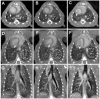

Small-animal imaging has a critical role in phenotyping, drug discovery and in providing a basic understanding of mechanisms of disease. Translating imaging methods from humans to small animals is not an easy task. The purpose of this work is to review in vivo x-ray based small-animal imaging, with a focus on in vivo micro-computed tomography (micro-CT) and digital subtraction angiography (DSA). We present the principles, technologies, image quality parameters and types of applications. We show that both methods can be used not only to provide morphological, but also functional information, such as cardiac function estimation or perfusion. Compared to other modalities, x-ray based imaging is usually regarded as being able to provide higher throughput at lower cost and adequate resolution. The limitations are usually associated with the relatively poor contrast mechanisms and potential radiation damage due to ionizing radiation, although the use of contrast agents and careful design of studies can address these limitations. We hope that the information will effectively address how x-ray based imaging can be exploited for successful in vivo preclinical imaging.